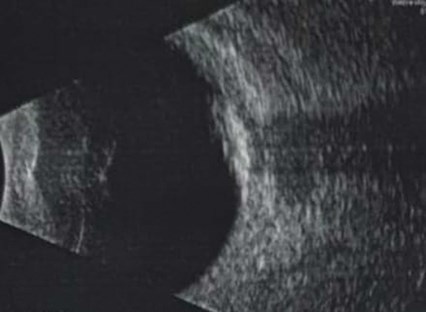

A nine-year-old boy presented for squint surgery with left exotropia and a one-month history of visual decline. Examination revealed poor light projection, a relative afferent pupillary defect, a slightly raised intraocular pressure and a yellowish plaque-like fundal lesion (Figure 1). Ultrasound showed specks of calcification, raising concern for Rb (Figure 2).

Figure 2: B Scan showing speck of calcification.